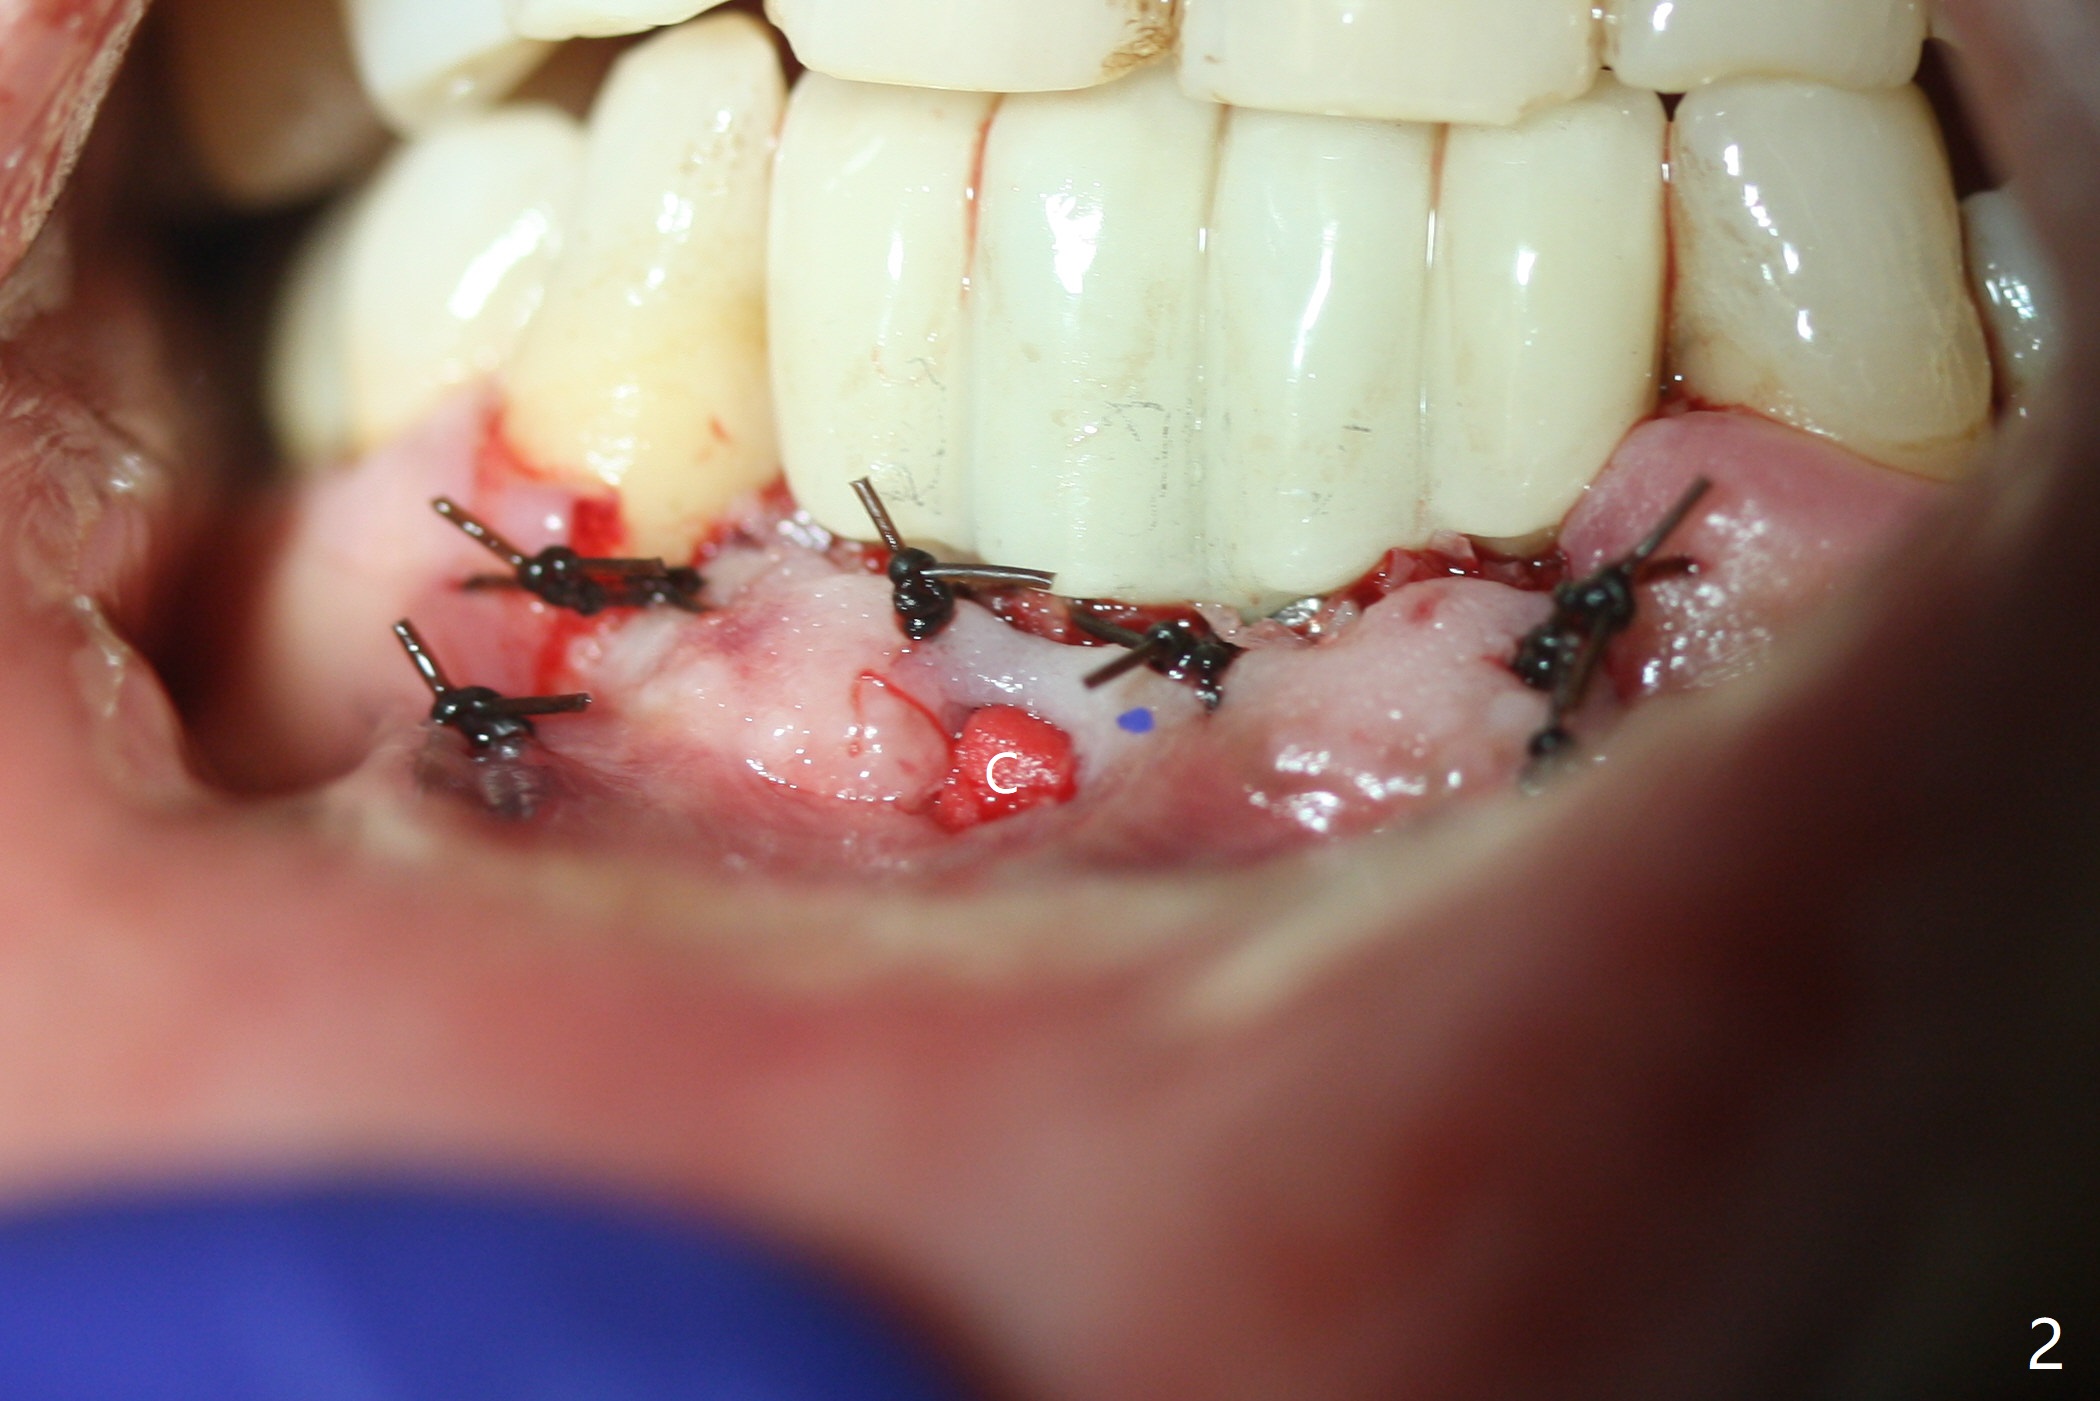

The fenetration found buccal to #25 two months post cementation persists, although asymptomatic, 4 months post cementation. Blood is drawn for PRF. In fact the implants at #24 and 25 are exposed buccal; there is limited amount of the buccal bone (Fig.1 *). After granulation tissue removal, Titanium brush is used to clean the implant threads. Allograft and Osteogen are mixed with PRF liquid to form gel, which is placed over the exposed implant threads. The bone graft is covered with a piece of PRF membrane and a piece of collagen membrane (Fig.2 C). Immediately postop PA (Fig.3) and CBCT (Fig.4) show that the implants have sufficient clearance between them. The implant thread exposure is most likely due to failure to place the implants deep enough and the implants are slightly large relative to the ridge (Fig.5-8). If the bone graft does not heal, new type of 1-piece implants (Fig.9,10 (green) smaller in diameter, 2 or 2.5 mm ) with longer abutment (pink) will be placed subcrestal buccal with guide.